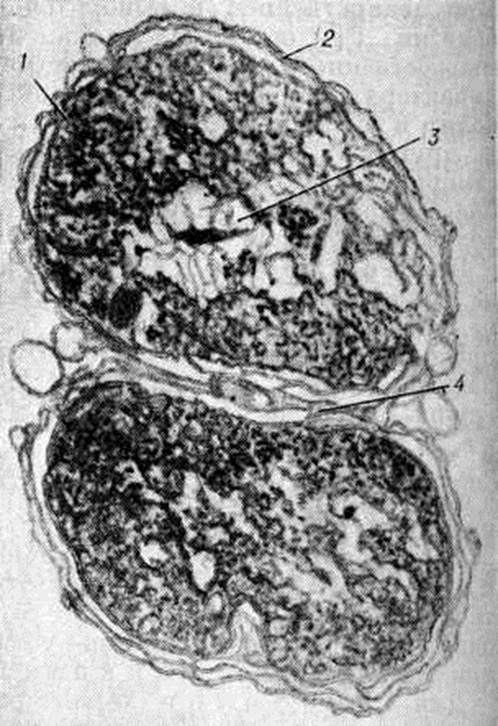

Рис. 1.

Электронограмма ультратонкого среза гонококка: 1 — цитоплазматическая мембрана; 2 — наружная стенка; 3 — ядро; 4 — перегородка.